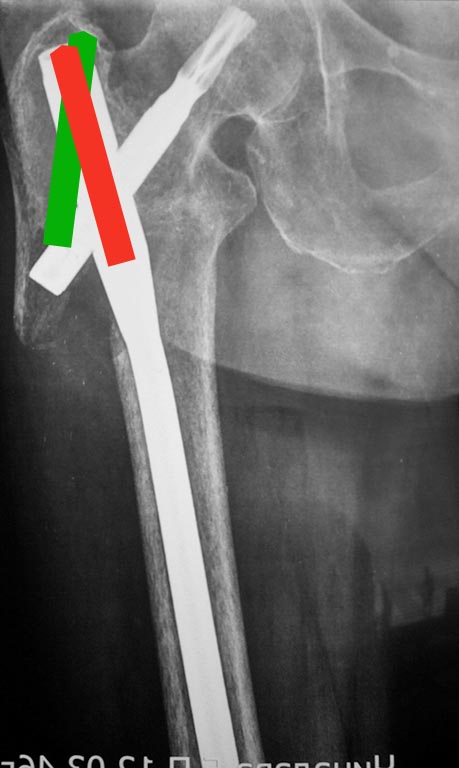

Ни угол в гвозде, ни мнимое или реальное отсутствие латеральной

стенки здесь ни при чем. Проблема обусловлена латеральной точкой

введения и медиальным направлением в центральном отломке. На приложенной

картинке зеленым обозначено должное положение гвоздя.